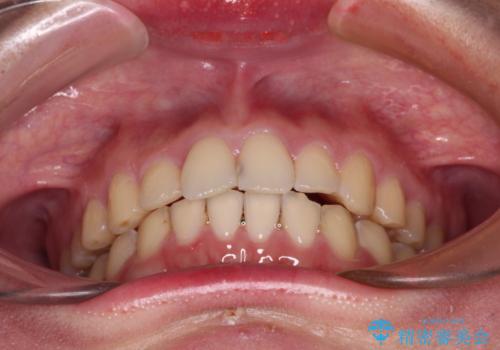

- 食いしばりが気になっていたとのことで来院された患者様です。

当初は睡眠時のマウスピースのみの製作をご希望でしたが、矯正治療の提案をしたところ、インビザラインにて矯正治療を行うこととなりました。

矯正治療中に食いしばりがより強くなることがあるため、半年に1回のペースでボツリヌストキシンによる咬合力緩和を並行して行うこととしました。

咬合力の緩和と食いしばりがちな咬み合わせが改善され、顎の負担が大幅に軽減されました。